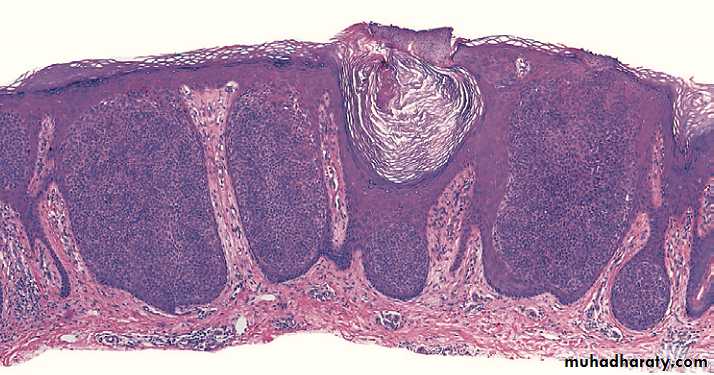

IV. Inverted Follicular Keratosis (IFK)

Asymptomatic solitary firm, white to light-tan or pinkish papules usually less than 1 cm in diameter on face or neck of middle-aged and older adults.They are typically stable and persistent lesions, but may regress.

Benign endophytic variant of irritated SK.

It is derived from the infundibulum of the hair follicle.

Histologically, The keratinocyte proliferation seems to surround one or several follicular canals that open to the surface. squamous eddies and inflammation are common.

Histopathology of IFK